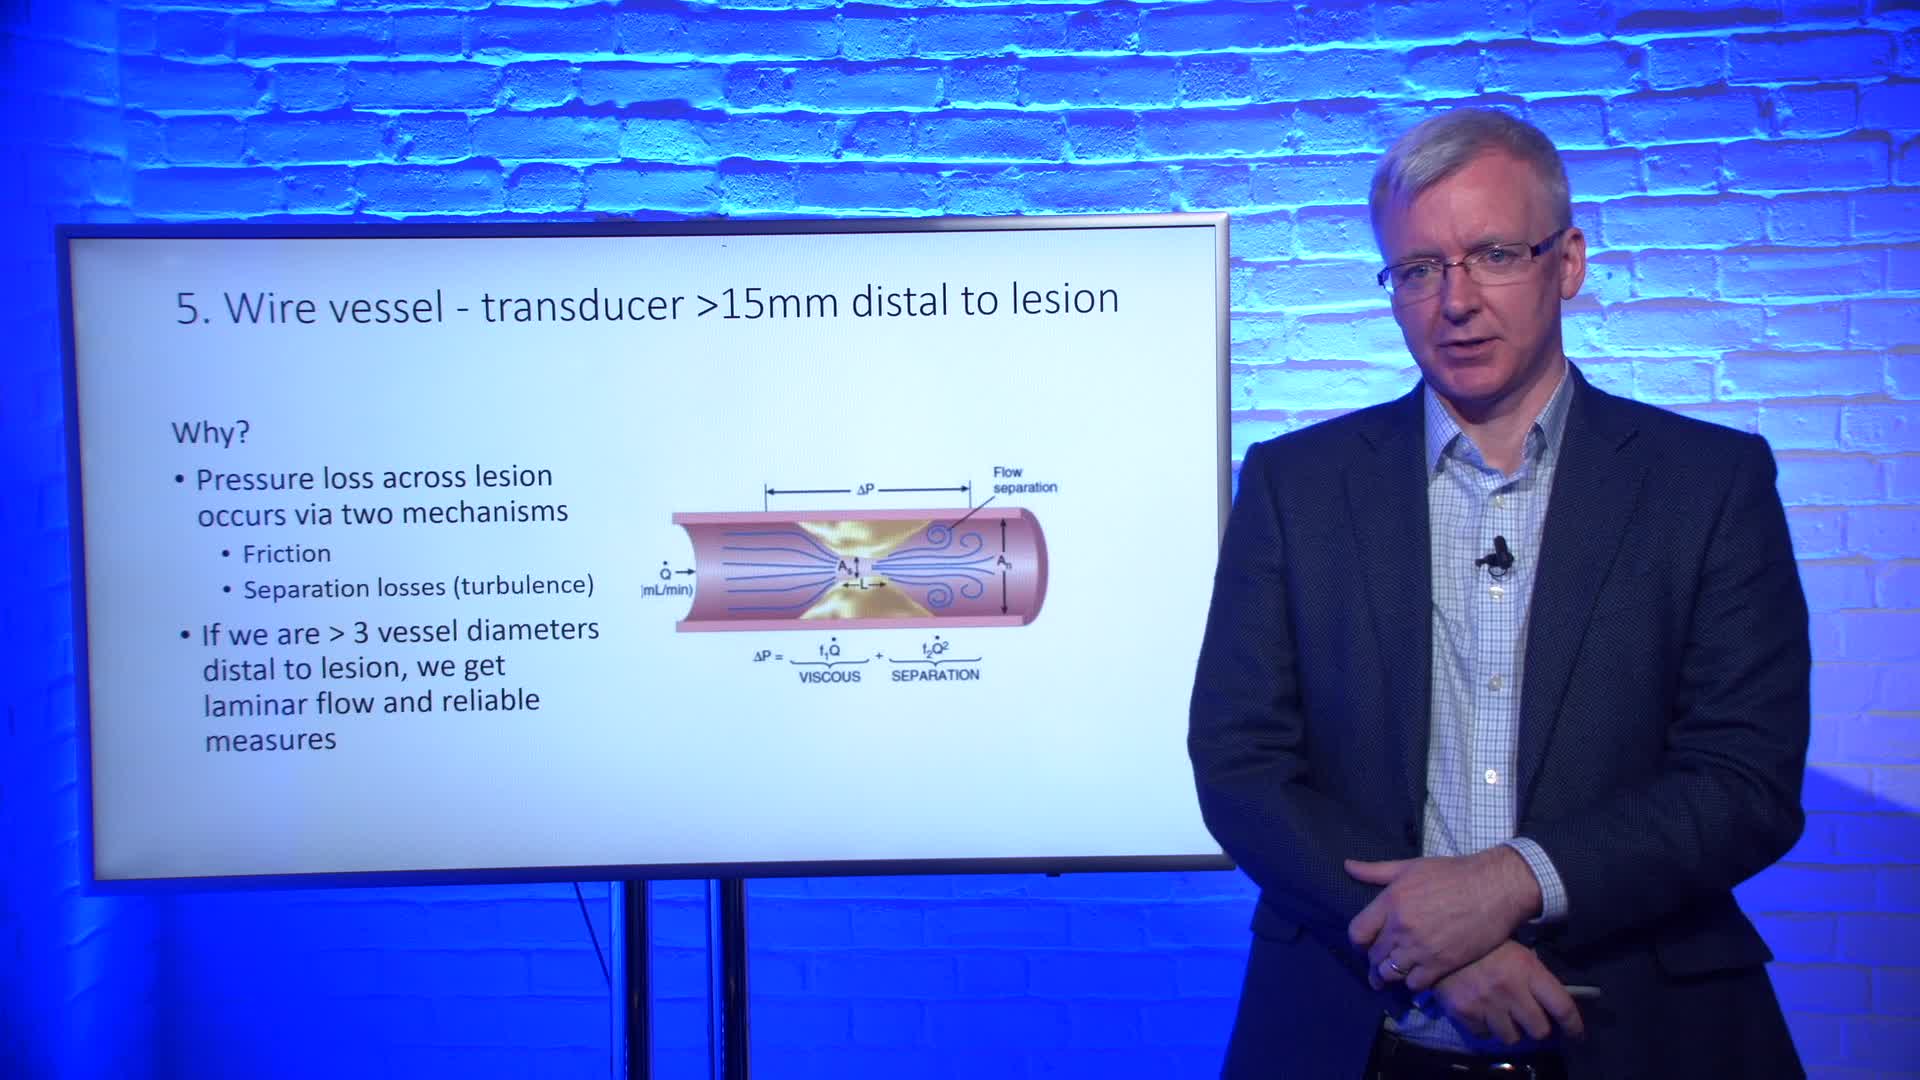

How to perform iFR and FFR, and best-practice measurement tips and tricks - Dr Ricardo Petraco

Essential steps for physiology-based PCI planning and guidance - Dr Allen Jeremias